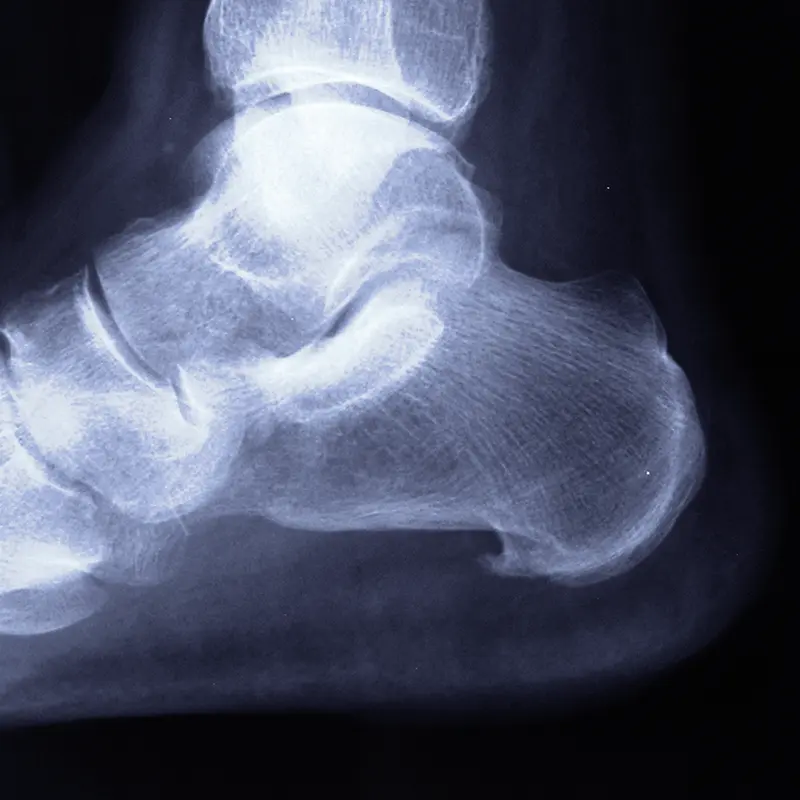

Las patologías que afectan a estas zonas del pie suelen tener un componente biomecánico importante y, en muchos casos, una evolución prolongada en el tiempo.

Engloban problemas como:

- Fascitis plantar, cuando no responde a tratamientos conservadores.

- Atrapamientos nerviosos (túnel del tarso, neuropatía de Baxter).

- Tendinopatías (tibial posterior, tendón de Aquiles, tendones peroneos).

- Cirugías del retropié (pie plano, artrosis, huesos accesorios).

- Cirugía reconstructiva (tratamiento de deformidades complejas y secuelas de lesiones en el pie y tobillo).

En estos casos, la indicación quirúrgica se valora de forma individual, teniendo en cuenta la biomecánica del pie y el impacto real del problema en la vida diaria.